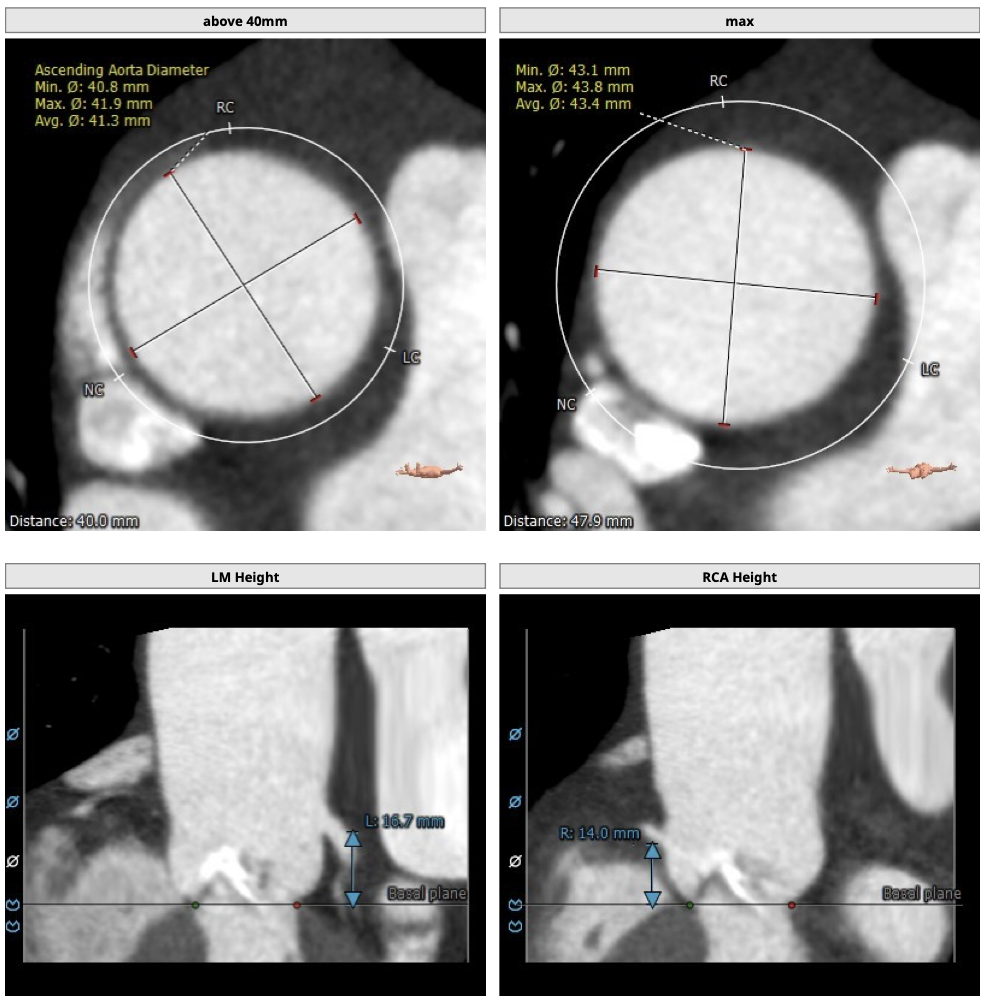

主动脉CT

患者为TYPE0型二叶瓣,轻中度钙化,瓣叶可见增厚,冠脉高度可,法式窦结构大,左室大小尚可,心肌肥厚,升主动脉可见增宽。

经分析研判,结合患者瓣上结构,拟采取downsize手术策略,优先选用L26号的VenusA-Valve瓣膜,备L23,使用VenusA-Plus确保瓣膜的精确释放,减少瓣膜移位风险,瓣膜释放后结合造影和超声情况,决定是否后扩。